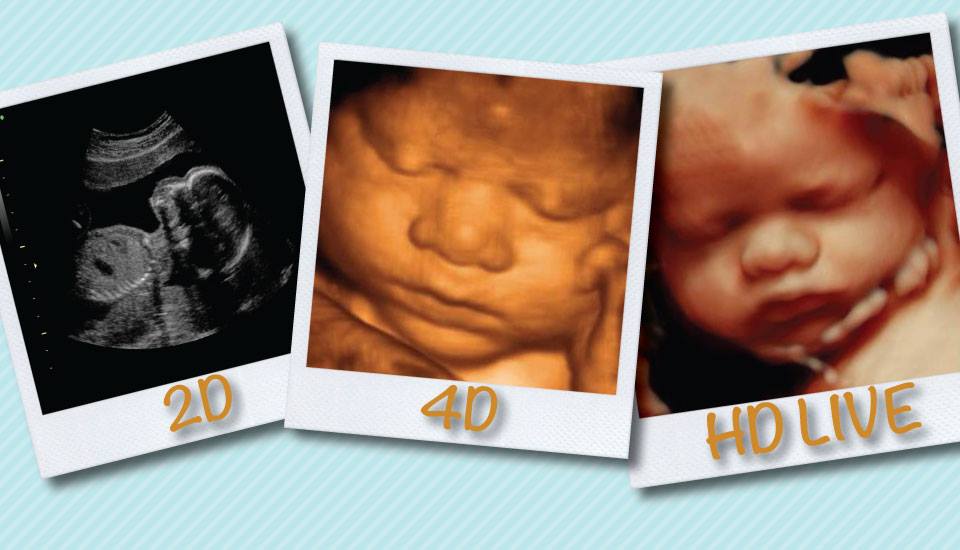

MiracleView3D4D's profile picture. For all expectant parents out there, now see your unborn baby with Arizona's Best 5D Ultrasound Technology!  18+ Years Serving Arizona Pregnant Families!

For all expectant parents out there, now see your unborn baby with Arizona's Best 5D Ultrasound Technology! 18+ Years Serving Arizona Pregnant Families!

Serving Arizona For 18+ Years For Elective Pregnancy Services. MiracleViewUltrasound.com 480-421-BABY All services listed on our website including Current Specials ❤ #pregnant #pregnacy #itsaboy #itsagirl

When choosing the best place for your 4D HD Live Ultrasound in Arizona, make sure you "Pick" a… instagram.com/p/CECphaRnXys/…